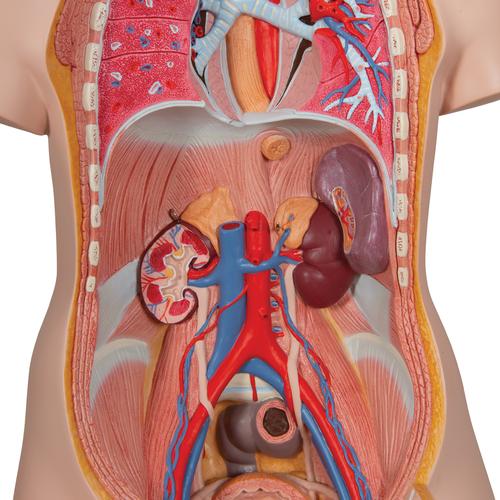

This meticulously crafted torso is expertly hand-painted with precision and made from high-quality plastic. All 3B torsos are designed and produced in Germany. This unisex human torso model features a distinctive open neck and back section extending from the cerebellum to the coccyx. It accurately depicts vertebrae, intervertebral discs, spinal cord, spinal nerves, vertebral arteries, and numerous other components in this vibrant representation of human anatomy. This human torso model includes the following detachable parts and organs:

- Pair of lungs

- 2-part heart

- Front section of kidney

- Front section of urinary bladder